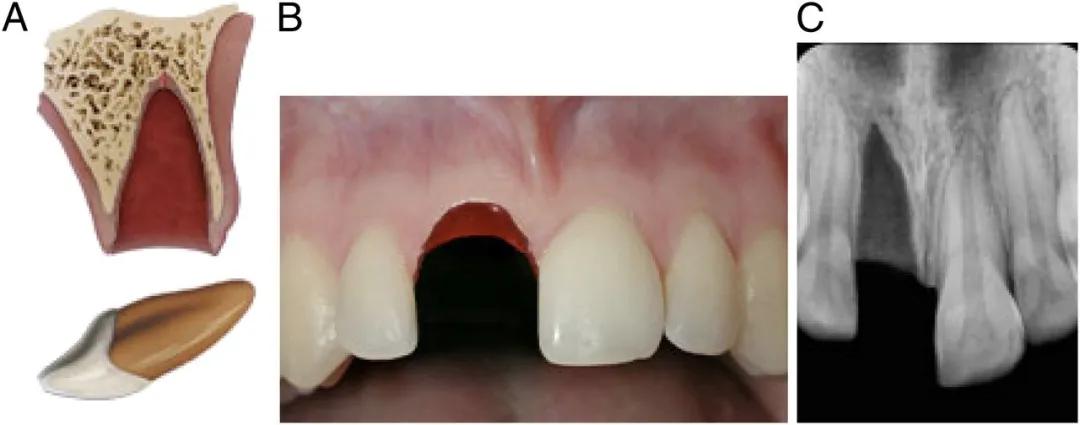

断牙治疗主要看断开的位置有没有暴露牙神经,分牙冠折断、牙根折断和冠根均折断等三种类型。

没有暴露牙神经,处理就比较简单。只需将牙釉质断面较锐利的地方磨光滑,不扎舌头即可。

也可以采用断冠再接的办法,把磕掉的那半截牙冠再粘回去。

如果牙齿摔断之后,牙冠碎了或者找不到了,就在保护牙髓之后,用材料对牙齿进行修复。

图注:断牙未暴露牙神经